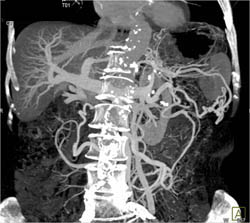

Subtle Tumor of the Body of the Pancreas